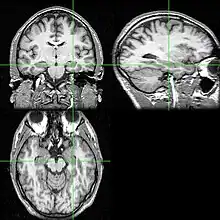

Neuroimaging tests may identify the cause for seizures and the seizure focus, the brain location where seizures begin.[4] In newly diagnosed epilepsy, magnetic resonance imaging (MRI) can detect brain lesion in up to 12 to 14% of persons with epilepsy.[31] However, for those with chronic epilepsy, MRI can detect brain lesion in 80% of the persons with epilepsy.[31] 3-Tesla MRI scan is advised for those with evidence of focal epilepsy such as temporal lobe epilepsy.[4] Abnormalities identified by MRI scan include hippocampal sclerosis, focal cortical dysplasia, other cortical developmental brain malformations, developmental and low-grade tumors, cavernous hemangioma, hypoxic-ischemic brain injury, traumatic brain injury and encephalitis.[4]

18F-fluorodeoxyglucose (18F-FDG) brain positron emission tomography (PET) may show a brain region of decreased glucose metabolism at a time between seizures; this hypometabolic region may correspond to the seizure focus, and PET scan is more sensitive for temporal lobe seizure focus localization compared to epilepsy arising from other brain lobes.[4] Single-photon emission computed tomography (SPECT) may show a region of decreased blood flow occurring 40-60 seconds after injection during the seizure; this reduced blood flow region may correspond to the seizure focus.[4]

Computed tomography (CT) scan is less sensitive than MRI scan for identifying small tumors, vascular malformations, cortical developmental brain malformations, and abnormalities in the medial temporal lobe.[31] CT scan is advised in emergencies when the suspected cause of epilepsy may be intracerebral hemorrhage, brain abscess, large cerebral infarction or subdural empyema.[4][31] A person who requires neuroimaging but cannot have an MRI scan due to implanted devices such as a cardiac pacemaker, defibrillator or cochlear implant may receive a CT scan. CT scan may better demonstrate calcium containing brain abnormalities causing epilepsy such as in tuberous sclerosis and Sturge–Weber syndrome.[4][31]